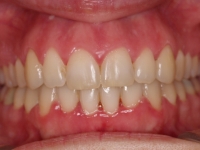

Radiografía de final de tratamiento